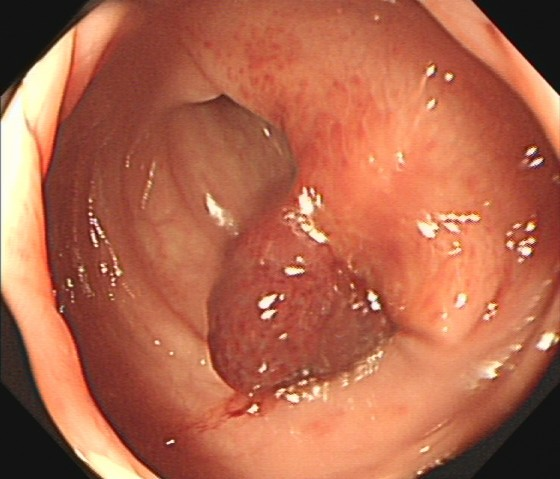

(1)赖女士(62岁,横结肠息肉,图1)

肠镜一照,息肉现形!形态各异的大肠息肉,离癌有多远?(图1)

图1

病理诊断:管状腺瘤,伴低级别上皮内瘤变。

解读:管状腺瘤是最常见的腺瘤性息肉。低级别上皮内瘤变意味着腺体结构和细胞出现了轻度到中度的异常改变,是明确的癌前状态。此阶段积极切除并定期复查,可有效阻断癌变进程。距离癌:一步之遥,癌前病变中期。